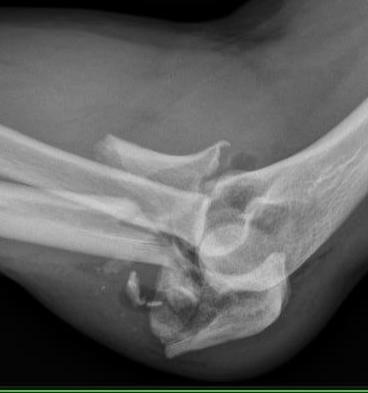

Proximal ulna / olecranon fracture

- posterior radial head dislocation most common in adults

- no fractures

Bado Type II most common in adults with posterior radial head dislocation